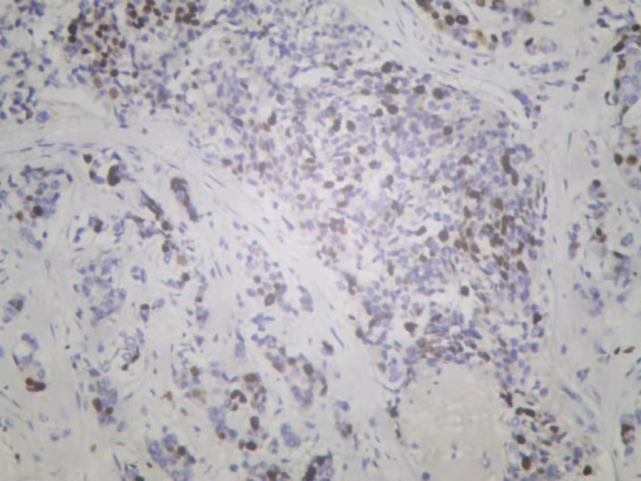

2021-11 乳腺超声:左乳内上象限11点钟至外下象限4点钟方向乳头中央区深面可见一个异常回声区,与导管关系密切,局部延伸至乳头中央区深面,范围约10.5×1.8cm,距皮4mm,形状呈不规则形,边界不清,肿块内部可见丰富紊乱的血流信号。左侧腋窝可见3-4个异常实质回声,大小不等,最大约2.7×1.5cm,形状呈不规则,边界欠清楚。

图1. 新辅助治疗前乳腺超声